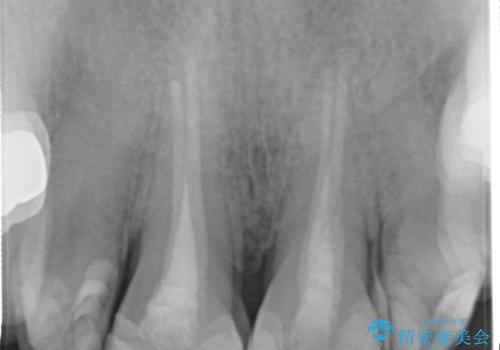

- 前歯の着色が気になるということを主訴に来院された患者様です。

以前に、根管治療をされているみたいなのですが、そのまま放置されていてどんどん着色がひどくなり来院されました。

神経の治療をしている歯は、時間と共に色がどんどん変色していきます。

また、神経、血液供給がなくなってしまうので歯も脆くなっていってしまう為、歯が割れてしまうリスクもあります。